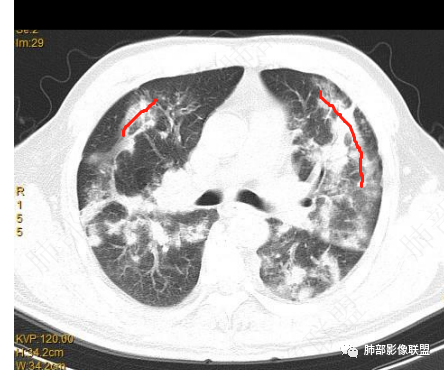

首先病灶是距离胸膜有间隙为主,其次是侧向融合,导致长轴与胸膜平行

距离胸膜的位置——提示小叶核心病灶

侧向融合

提示病灶位于小叶核心,逐步增大,到了一定大小之后相互连接,也就是侧向融合

还没有融合的

已经融合的

相对而言:已经融合的,边缘平直、光滑一些,周围纤维化明显一些,没融合的边缘模糊一些,周围GGO多一些;提示融合的病灶更早,已经开始有纤维化改变特点;而没融合的属于后发一些的病灶,纤维成分还不够

提示融合:除了有病灶增大的原因,与纤维化也很大关系

至于这种反晕征状:我认为是外周一层的小叶核心病灶与偏内侧的小叶核心病灶的融合,不是大片状病灶周围的修复所指。